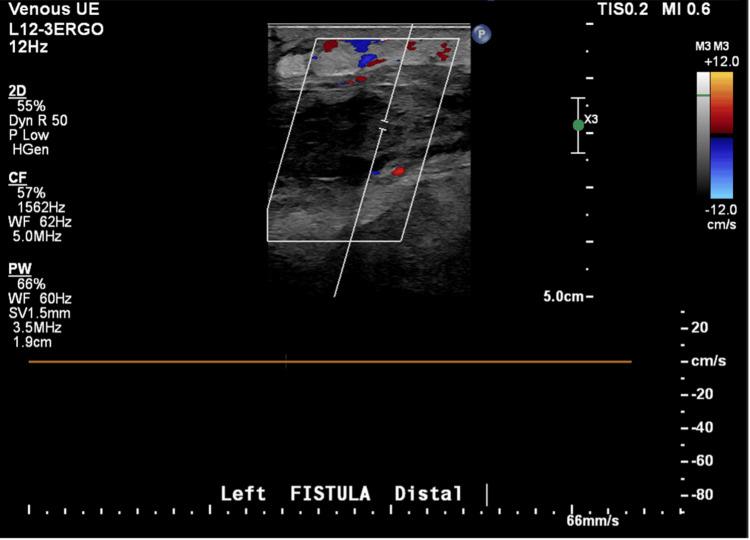

Glucagon-like peptide-1 (GLP-1) receptor agonists are widely used due to their significant anti-atherosclerotic, cardiovascular, and renoprotective benefits. However, potential adverse effects must also be considered. Here, we present a rare case of GLP-1 receptor agonist-induced thrombotic complications in a middle-aged African American female, contributing to the limited existing literature on this topic. A 55-year-old African American female with a past medical history of deceased donor renal transplantation presented with pain, swelling, and erythema localized to the left arteriovenous (AV) fistula. She also reported fever, chills, and the absence of a palpable thrill over the fistula for approximately one week before presentation. On physical examination, she exhibited significant swelling of the left upper limb with no detectable thrill over the AV fistula. Venous and arterial Doppler ultrasound of the left upper extremity revealed extensive thrombosis involving the left AV fistula, brachiocephalic vein, and both the radial and ulnar arteries. An extensive prothrombotic workup, including evaluations for inherited and acquired hypercoagulable states, was unremarkable. The only notable change in her medical regimen was a recent dose escalation of her GLP-1 receptor agonist. Given the temporal association and absence of alternative causes, the thrombosis was attributed to the GLP-1 receptor agonist, which was subsequently discontinued. No further thrombotic events occurred during follow-up. This case highlights one of the rare thrombotic events of commonly used drugs, such as GLP-1 receptor agonists. This case also underscores the importance of life-threatening events of commonly used drugs, adding to the existing literature.